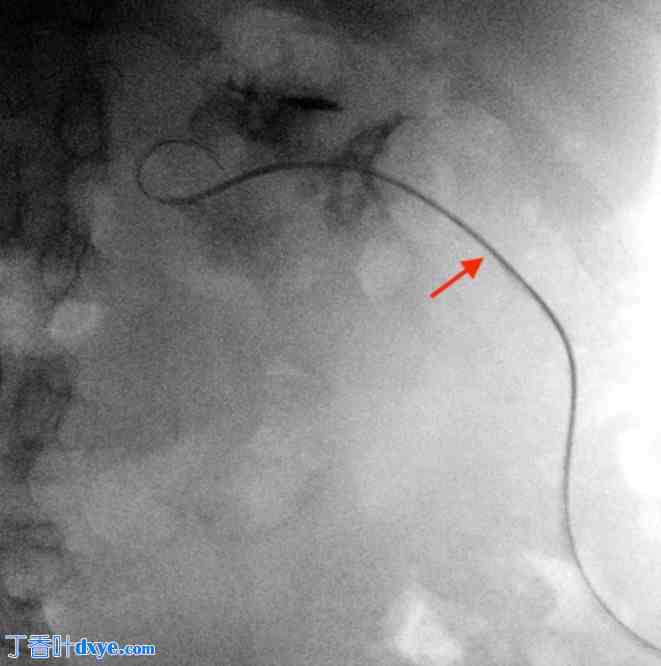

一名43岁男性患者因右肾绞痛和发热入院。非增强CT扫描显示肾盂内有一枚2.5厘米的梗阻性结石(图1)。患者接受了静脉抗生素治疗,介入放射科医生在中肾盏内插入了一根导尿管,引流出脓性分泌物。三周后,一位经验丰富的泌尿内镜医师利用预先建立的导尿管通道,行俯卧位经皮肾镜取石术(PCNL)。术中,首先将一根Roadrunner PC亲水导丝(Cook Medical)经导尿管送入中肾盏,试图将导丝穿过嵌顿结石(图2)。随后取出导尿管。接着,将一根Kumpe 5 Fr通路导管(Cook Medical)沿导丝置入,旨在引导其到达近端输尿管。透视下经Kumpe导管注射造影剂,可见一粗大的管状结构,造影剂迅速向上排出(图3)。在进行增强透视检查后,确认Kumpe导管尖端位于下腔静脉腔内(图4)。随即召开紧急多学科会诊,包括泌尿内镜医师、血管外科医师、介入放射科医师和麻醉医师。患者血流动力学稳定,无活动性出血或呼吸压力升高的迹象。在注射造影剂的同时,小心地将Kumpe导管回撤至肾中盏,未发生经导管进入肾单位或腹膜后间隙的出血。随后,介入放射科医师通过新建立的通道将8 Fr NT导管插入肾上盏。术中患者血流动力学稳定。术后静脉注射造影剂的CT扫描未见造影剂晕染或出血迹象。之后,患者成功接受了经皮肾镜取石术(PCNL),从肾上盏取出结石。

图 2.

一根 Roadrunner 亲水导丝经肾造瘘管插入肾盂。